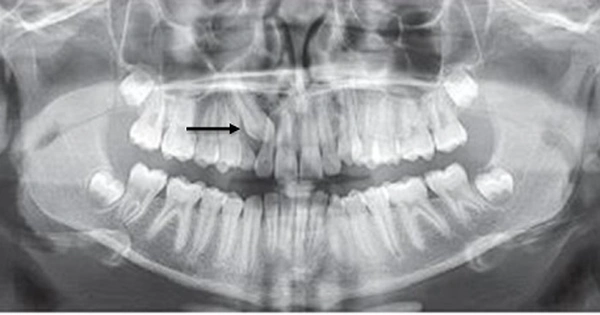

Chụp X-quang để xác định vị trí và hướng mọc của răng

Chụp phim toàn cảnh (Panorex): Giúp bác sĩ có cái nhìn tổng quát về sự sắp xếp của tất cả các răng, xác định vị trí chung của răng ngầm.

Chụp phim Cone Beam CT (CBCT): Tại Nha khoa Dr. Green, chúng tôi ưu tiên sử dụng CBCT vì nó cung cấp hình ảnh 3 chiều chi tiết. Phim CBCT giúp bác sĩ xác định chính xác:

- Vị trí và độ sâu: Răng nằm ở mặt môi hay mặt khẩu cái (vòm miệng), nằm cách mặt nhai bao nhiêu.

- Hướng mọc: Răng nằm ngang, xiên hay thẳng đứng.

- Mối quan hệ với các cấu trúc lân cận: Đặc biệt là mối quan hệ với chân răng cửa bên (để đánh giá nguy cơ tiêu chân).